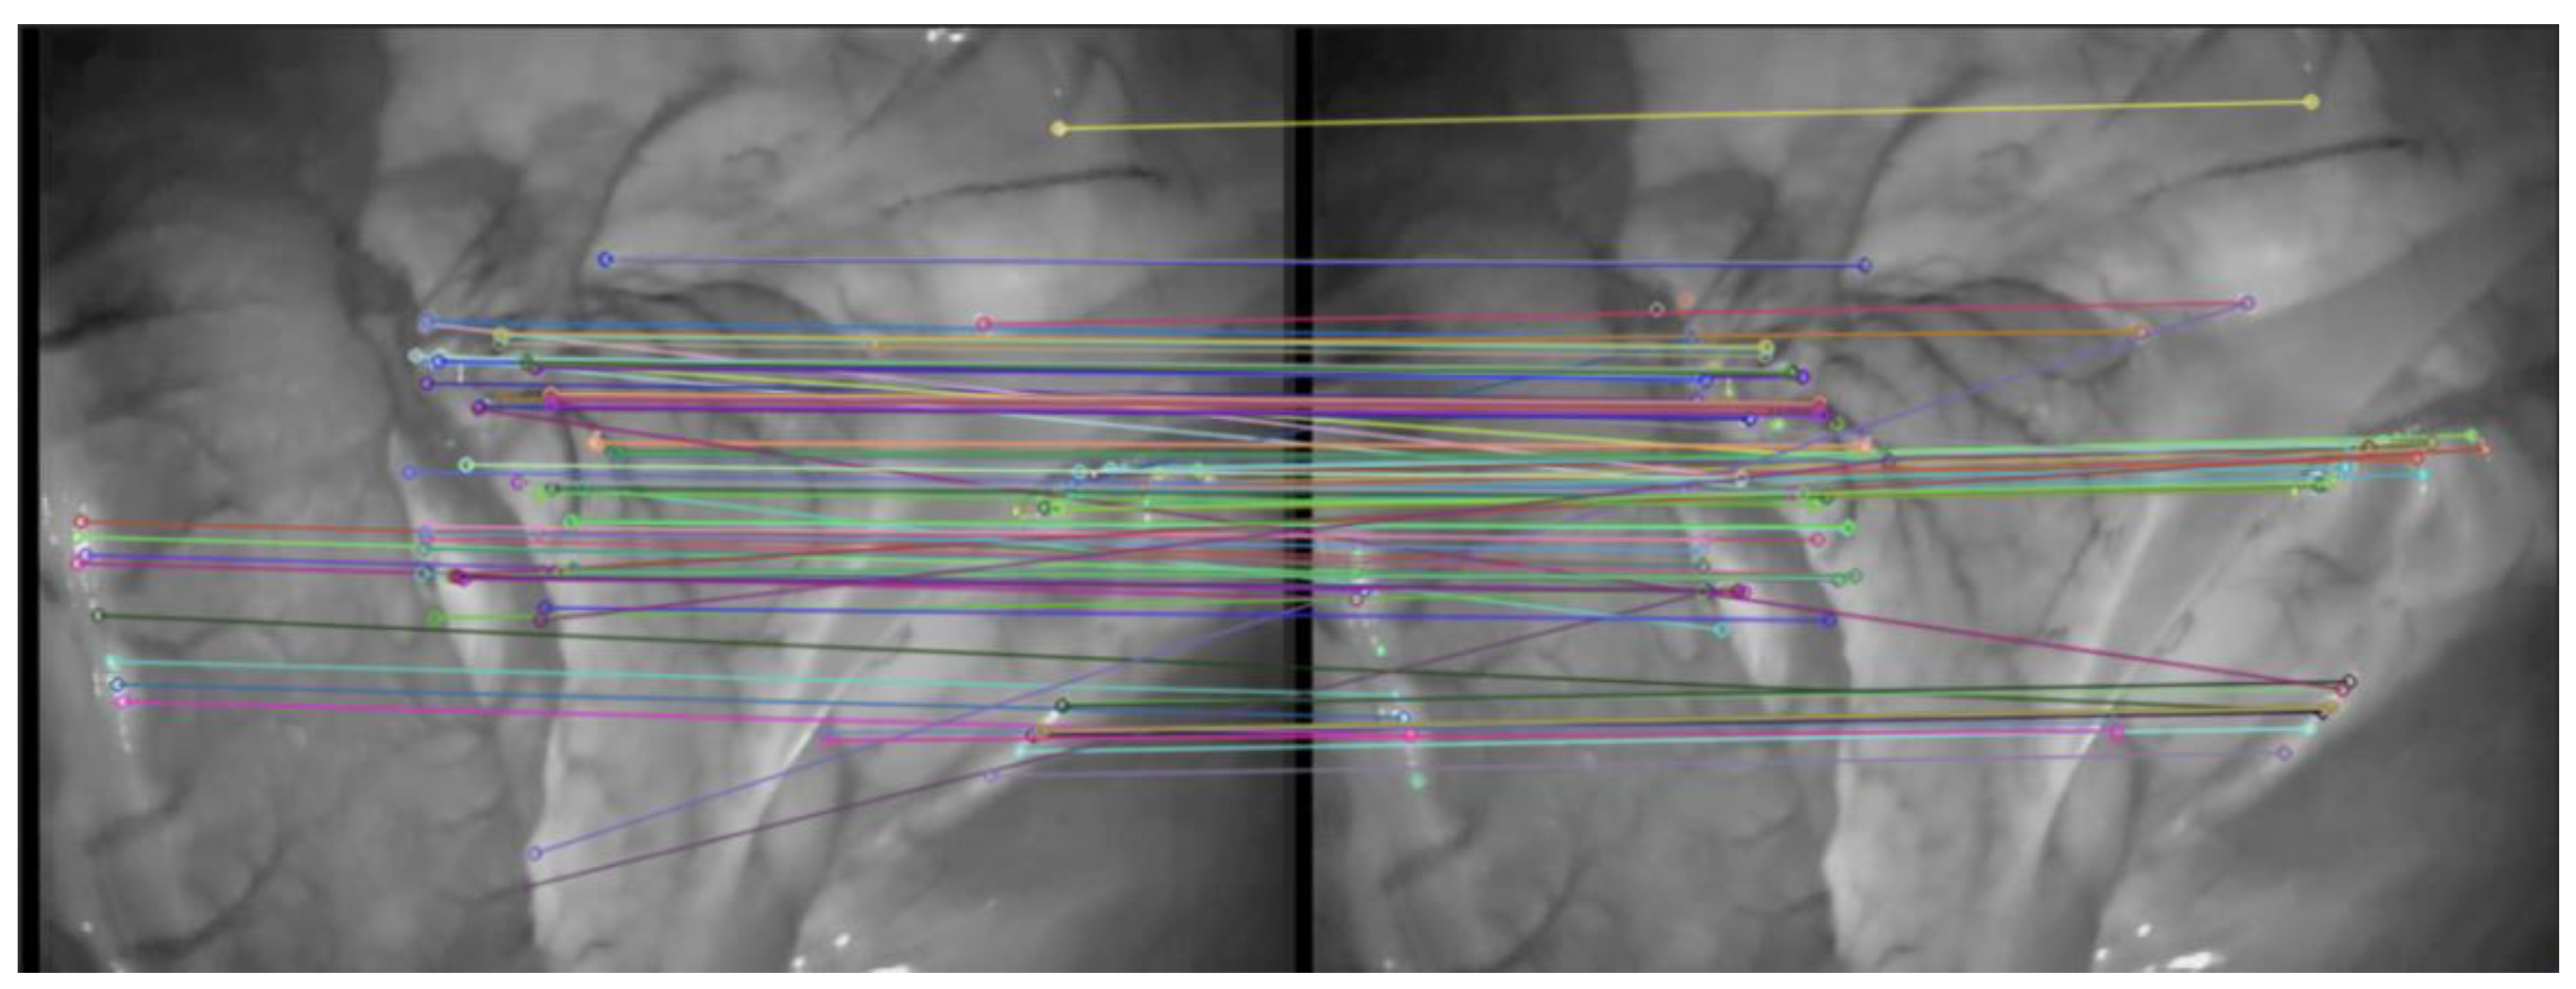

The effect of traditional ORB algorithm and AKAZE-ORB algorithm on extracting feature points of abdominal image frame is shown in Figure 4. The effect of AKAZE-ORB algorithm on abdominal image frame feature point matching is shown in Figure 5.

Figure 4. Comparison of ORB and AKAZE-ORB algorithm for feature points extraction. (a) ORB; (b) AKAZE-ORB.

Symmetry 14 00185 g004

Figure 5. Feature points matching results obtained by AKAZE-ORB.